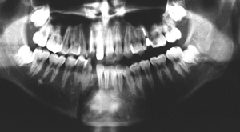

レントゲンで見ると、こんな具合です。

右下顎側切歯と犬歯の間、左の親不知のところに亀裂が見えますか?……